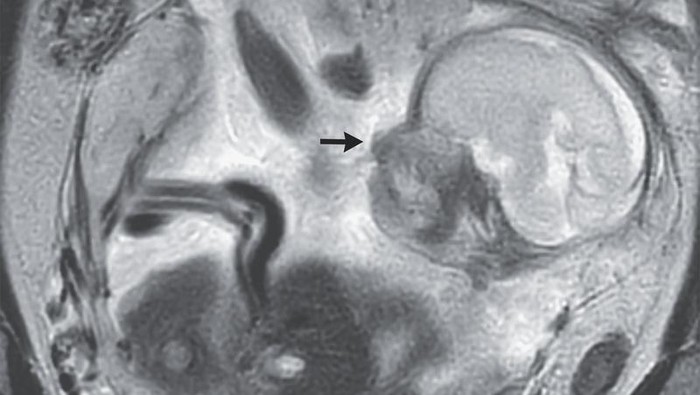

Awalnya gegara gejalanya tak kunjung mereda, wanita tersebut menjalani pemindaian perut. Dari sanalah baru ditemukan bahwa ada janin tumbuh dengan normal di rongga perutnya, tepatnya di antara perut dan ususnya.

Dokter mendiagnosis wanita yang tidak disebutkan namanya itu menderita kehamilan ektopik atau kehamilan di luar rahim, dan terjadi di perut. Bayi berada di rongga peritoneum, atau area tempat organ vital berada.

Sementara plasenta sang janin menempel di bagian atas panggul.